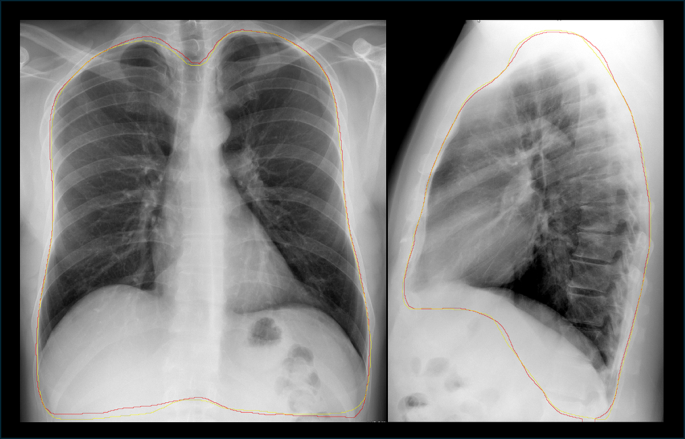

To avoid spurious associations related to extra-pulmonary characteristics (e.g., patient identification labels)91,92,93, the 3,206 (1,682 Frontal + 1,524 Lateral) CXR images were manually segmented by an Expert Reviewer (Author 1) using a modification of the GUI100. These segmentations followed the inner surface of the ribs and diaphragm to delineate the thoracic-cavity contents (e.g., lungs) from the apex to the posterolateral costophrenic sulci, using the L1-L2 disc space as a reference whenever they were obscured, such as by a pleural effusion102.

The resulting segmentations of the thoracic contents were used to create by supervised learning the Thoracic-Content Segmentator for automatic thoracic segmentation as the first PVPI component. The Thoracic-Content Segmentator was developed based on the DeepLabV3 semantic segmentation architecture103, with ResNet-50 as a backbone104. The final Dice coefficients105,106 achieved by the Thoracic-Content Segmentator were 0.98 for Frontal views and 0.97 for Lateral views [Fig. 7].

Automatic thoracic-content segmentation on the CXR Frontal view (Left) and the Lateral view (Right). The original expert ground-truth segmentations (yellow) and the model inference segmentations produced by the Thoracic-Content Segmentator (red) corresponded very closely.